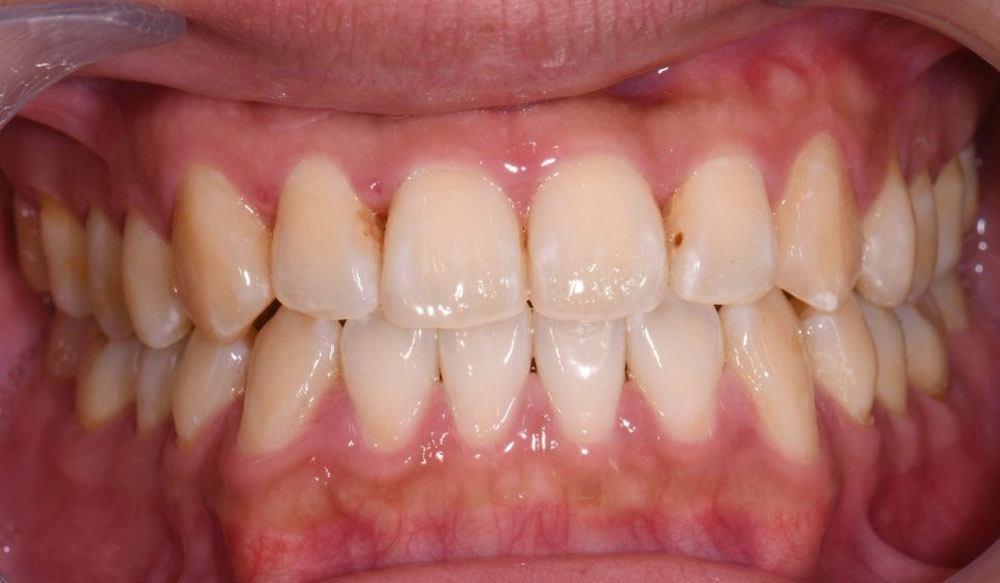

Mandibular Advancement

Invisalign® treatment with mandibular advancement is aimed for growing patients presenting with retrognathic Class II malocclusions in permanent dentition or stable late mixed dentition. The special feature of precision wings are integrated into the Invisalign aligners.

Patient Information:

Age: 14

Gender: male

Invisalign Treatment Option: Invisalign Teen with MA

Total Treatment Time:

36 months